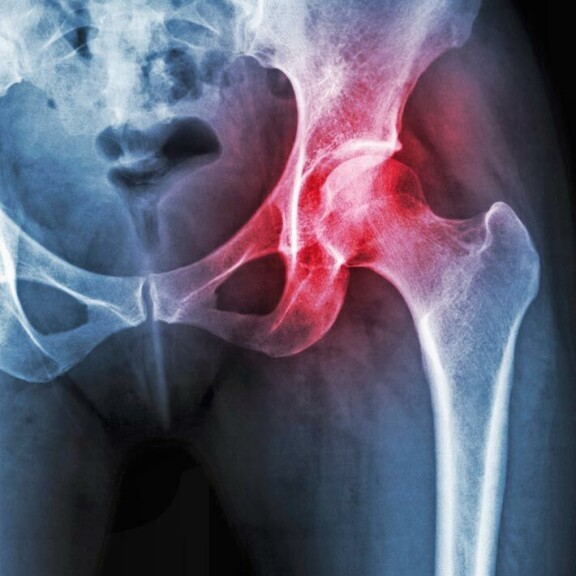

Suomessa yli 45-vuotiaista noin kuusi prosenttia sairastaa lonkkanivelrikkoa. Brittitutkijat ovat havainneet lonkkaniveleen pistettävän kortikosteroidipistoksen helpottavan potilaiden kipuja ja parantavan toimintakykyä. Pistoksen vaikutus on tehokkain 2-4 kuukauden sisällä pistoksesta. Toistaiseksi kortikosteroidipistoksia käytetään yleisemmin polven nivelrikon hoidossa.